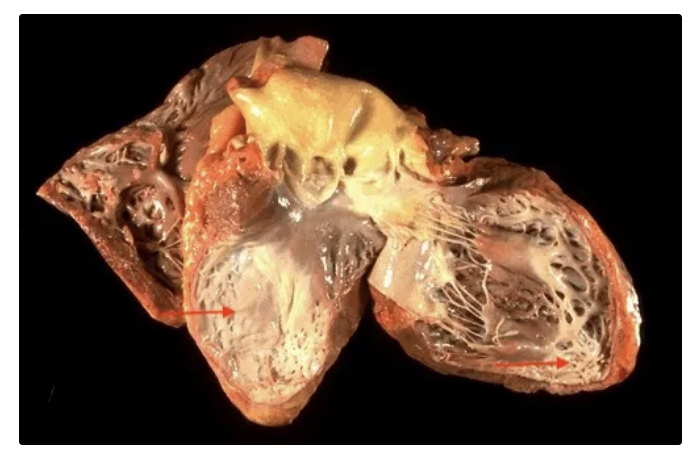

Cardiopatía isquémica crónica

Hemopericardio: acumulación de sangre, principalmente por rotura cardiaca